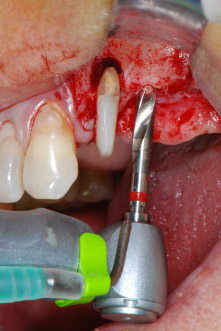

Le sedi di impianto sono state preparate in corrispondenza dei siti 25 e 26 con strumentazione rotante, utilizzando un manipolo contrangolo con una velocità di trasmissione 20:1 con motore potente di nuova generazione (Implantmed di W&H) (Fig. 8).

Gli impianti (Restore, Keystone Dental,, diametro 3,75 mm, lunghezza 8,0 mm) sono stati posizionati con il motore per impianto (Figg. 11 e 12).